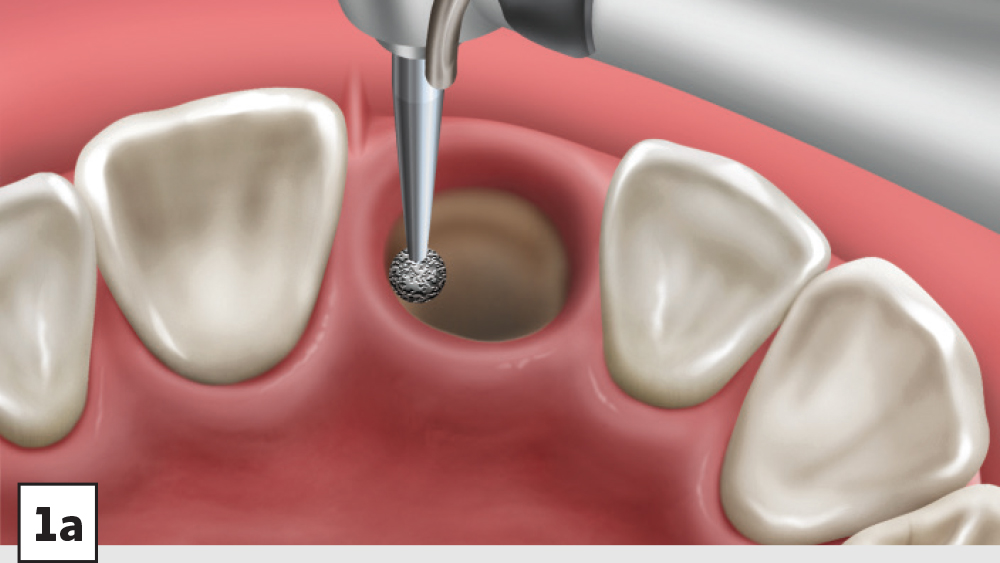

Five-Walled Socket Bone Grafting Technique (Figs. 1a–1d, 2a–2d)

1. Reflection: After extraction, a mucoperiosteal flap should not be reflected in most circumstances. However, a small subperiosteal pouch may be made around the margins of the extraction socket to allow for ease of membrane placement and suturing.

2. Preparation: The extraction socket should be free of soft-tissue remnants and bleeding should be present. If bleeding is not present, the remaining walls should be decorticated. Care should be exercised around adjacent teeth or vital structures. Bleeding from decortication will facilitate early vascularization and initiate the healing process.

3. Graft Material: The graft material (e.g., Newport Biologics Mineralized Cortico/Cancellous Allograft Blend) should be hydrated with sterile saline (0.9% sodium chloride) or platelet-rich fibrin (PRF) and then gently condensed into the socket. Small increments of material should be added into the socket, and a bone-packing instrument, such as the Bone Carrier and Spoon included with the 12-piece Newport Biologics Implant and Bone Grafting Instrument Kit (Glidewell Direct), should be utilized to condense the material to avoid air spaces (Fig. 3). Usually, when “push-back” of the material is present, the socket is packed sufficiently. Care should be exercised to avoid packing the graft material too densely, as this may interfere with angiogenesis and delay the healing process.

1. Membrane: A Newport Biologics Resorbable Collagen Plug should be cut in half and hydrated with 0.9% sodium chloride. The plug is compressed and placed over the socket, extending the collagen underneath the reflected subperiosteal pouch to increase retention.

2. Closure: Closure should be completed with a high-tensile suture material, such as polyglycolic acid (PGA) or PTFE, with a crisscross suture technique (Table 2). Care should be exercised to avoid suturing through the membrane. Gut sutures (plain, chromic) should be avoided, as they have a compromised tensile strength and will increase the probability of bone graft and membrane loss.